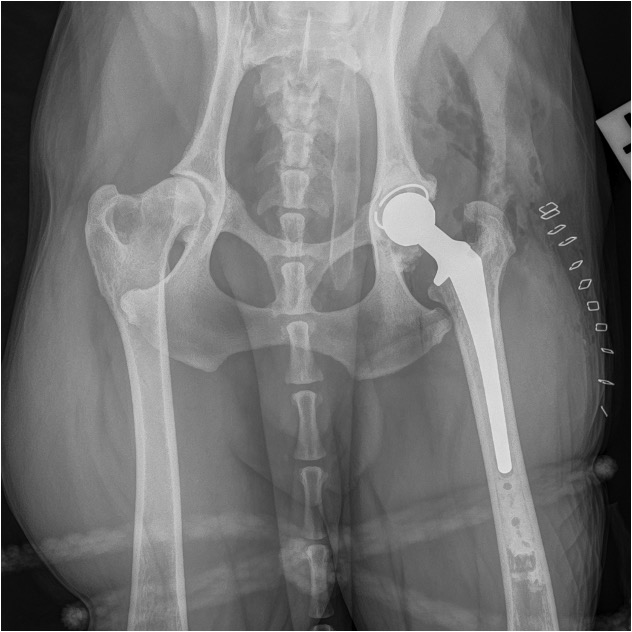

Total Hip Replacement

- This is the treatment of choice for the intractably painful hip that has not responded sufficiently to medical management. The most common age for a dog to have a hip replacement is 1-2 years of age and this is usually because the pain from dysplasia is such that it cannot be controlled with medical management. The hip replacement should last for the lifetime of the dog.

- Total hip replacement can be performed on almost any size of dog. It is generally a very successful procedure but complications can occur and so it is essential that clients are carefully counselled by an experienced surgeon so that they can understand the likely benefits but also the potential risks associated with the procedure.